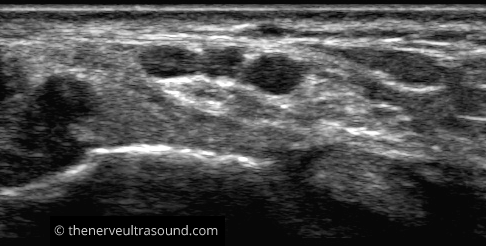

A: Medial malleolus

At the level of the medial malleolus the tibial nerve lies dorsal to the posterior tibial artery with its accompanying veins.